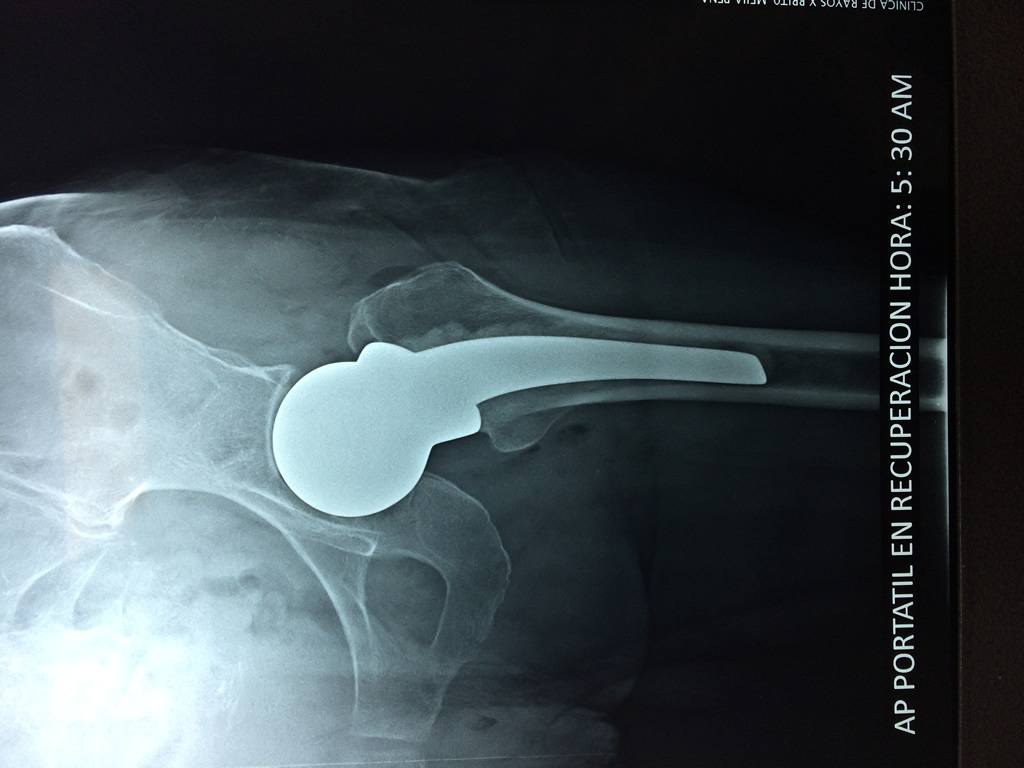

Húmero - Cadera